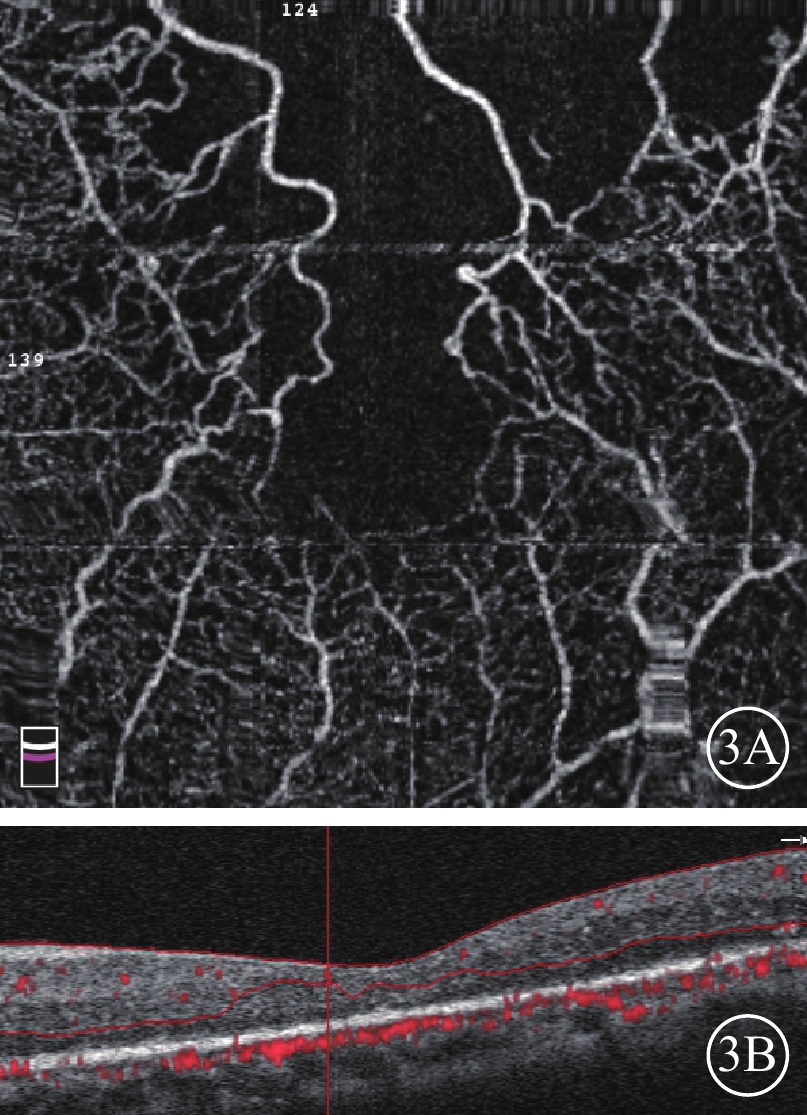

依據黃斑水腫程度將72例75只眼分為M300組(CRT≥300 μm)、L300組(CRT<300 μm),分別為38例39只眼和34例36只眼。M300組38例中,男性27例,女性11例;平均年齡(59.31±9.09)歲;平均CRT(474.00±157.03)μm。39只眼中,Major型、Macular型分別為28、11只眼。FAZ破壞27只眼。黃斑水腫已消退3只眼;黃斑中心凹變薄呈萎縮、缺血狀態1只眼;黃斑囊樣水腫14只眼,彌漫性水腫2只眼,視網膜下液型水腫3只眼;混合型水腫19只眼,其中存在視網膜下液14只眼。L300組34例中,男性13例,女性21例;平均年齡(52.44±9.75)歲。平均CRT(244.33±34.55)μm‘。36只眼中,Major型、Macular型分別為24、11只眼。FAZ破壞23只眼。黃斑水腫已消退14只眼;黃斑中心凹變薄呈萎縮、缺血狀態(圖3)7只眼;黃斑囊樣水腫9只眼,彌漫性水腫2只眼,混合型水腫2只眼。

圖3

BRVO患眼OCTA像及B-scan像。3A示OCTA像,FAZ面積明顯擴大,上方大片無血流區;3B示B-scan像,視網膜無水腫,厚度變薄

圖3

BRVO患眼OCTA像及B-scan像。3A示OCTA像,FAZ面積明顯擴大,上方大片無血流區;3B示B-scan像,視網膜無水腫,厚度變薄

依據黃斑水腫程度將72例75只眼分為M300組(CRT≥300 μm)、L300組(CRT<300 μm),分別為38例39只眼和34例36只眼。M300組38例中,男性27例,女性11例;平均年齡(59.31±9.09)歲;平均CRT(474.00±157.03)μm。39只眼中,Major型、Macular型分別為28、11只眼。FAZ破壞27只眼。黃斑水腫已消退3只眼;黃斑中心凹變薄呈萎縮、缺血狀態1只眼;黃斑囊樣水腫14只眼,彌漫性水腫2只眼,視網膜下液型水腫3只眼;混合型水腫19只眼,其中存在視網膜下液14只眼。L300組34例中,男性13例,女性21例;平均年齡(52.44±9.75)歲。平均CRT(244.33±34.55)μm‘。36只眼中,Major型、Macular型分別為24、11只眼。FAZ破壞23只眼。黃斑水腫已消退14只眼;黃斑中心凹變薄呈萎縮、缺血狀態(圖3)7只眼;黃斑囊樣水腫9只眼,彌漫性水腫2只眼,混合型水腫2只眼。

圖3

BRVO患眼OCTA像及B-scan像。3A示OCTA像,FAZ面積明顯擴大,上方大片無血流區;3B示B-scan像,視網膜無水腫,厚度變薄

圖3

BRVO患眼OCTA像及B-scan像。3A示OCTA像,FAZ面積明顯擴大,上方大片無血流區;3B示B-scan像,視網膜無水腫,厚度變薄